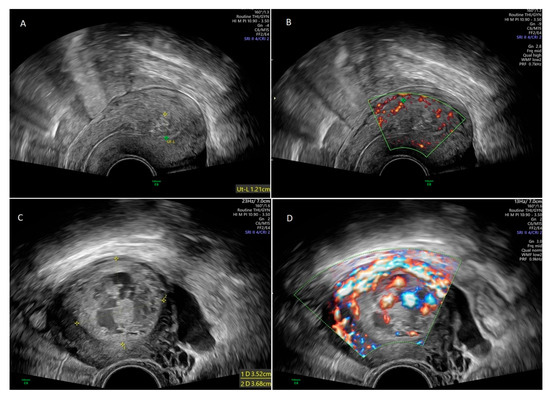

Uterine artery embolization (UAE) was performed by experienced interventional radiologists using standard angiographic techniques under local anesthesia. Importantly, embolization was performed in a targeted and selective manner, occluding only the arterial branches supplying the retained tissue rather than the entire uterine arteries. This selective approach, achieved with a microcatheter, minimized the risk of ischemic complications. Absorbable gelatin sponge particles (Marbagelan) were used as the main embolic agent, providing temporary occlusion (3–6 weeks) and allowing arterial recanalization, thereby helping preserve uterine perfusion and fertility. The procedure was technically successful in all cases, and patients were monitored for 12–24 h for possible complications such. Possible complications related to the procedure itself and during the postoperative period include bleeding from the puncture site, ischemic or cramping pain during or after the procedure, infection, allergic reaction [5,6]. No major adverse events were observed. Figure 2 shows uterine angiography before and after UAE.

Figure 2. Right uterine arteriogram in the patient before prophylactic embolisation with absorbable gelatin sponge particles (A). Postembolisation uterine arteriogram demonstrating successful embolization (B).